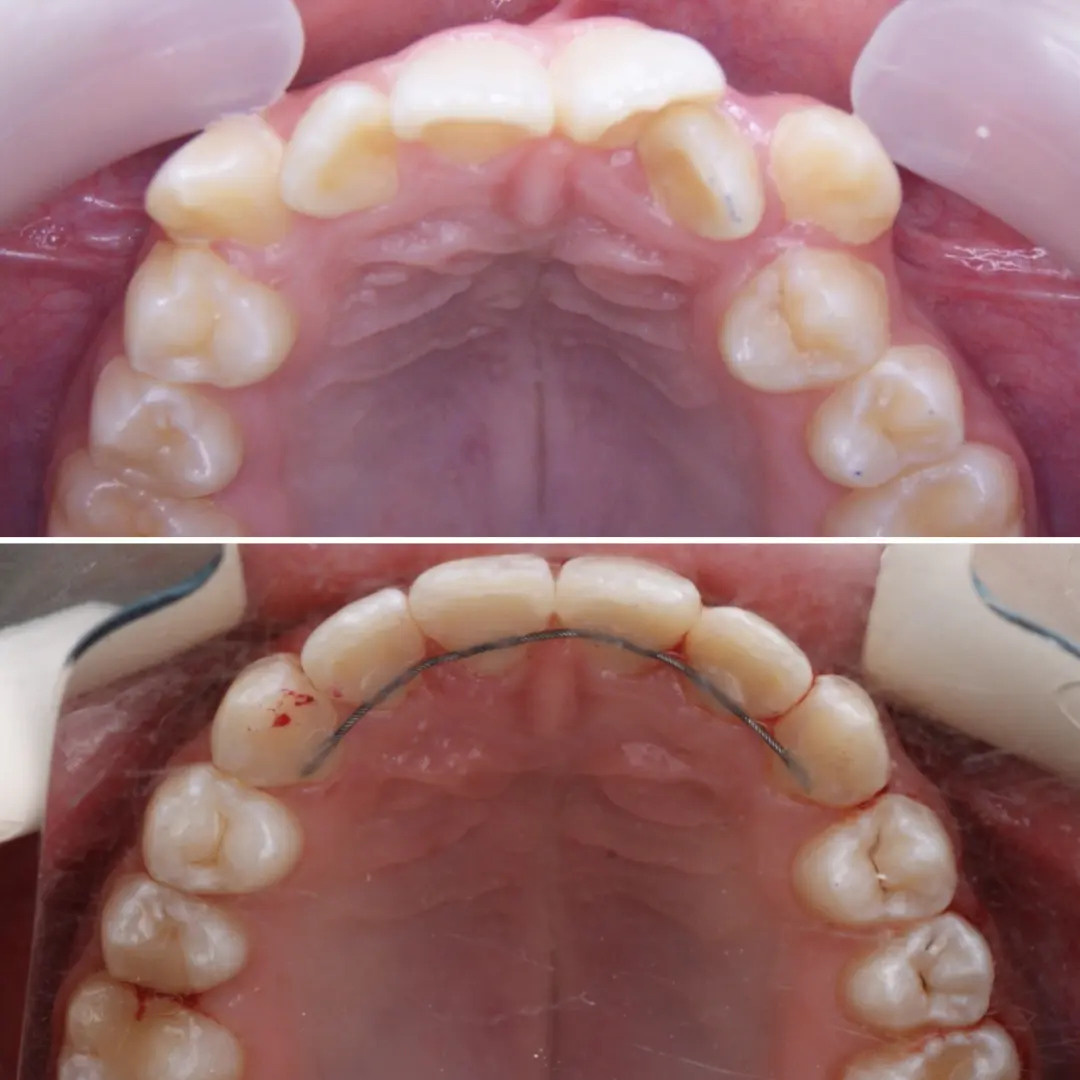

🔷️ Промежуточный результат лечения на аппарате Марко Роса (6 месяцев). Пациенту 7 лет. Самое удивительное - как "отвечает" на лечение нижняя челюсть: расширяется, меняется её положение и корректируется дистальный прикус, выравниваются нижние зубы, хотя никаких аппаратов на нижней челюсти не было!

P.S. Каждый случай уникальный, чаще нижнюю челюсть мы всё таки расширяем тоже.